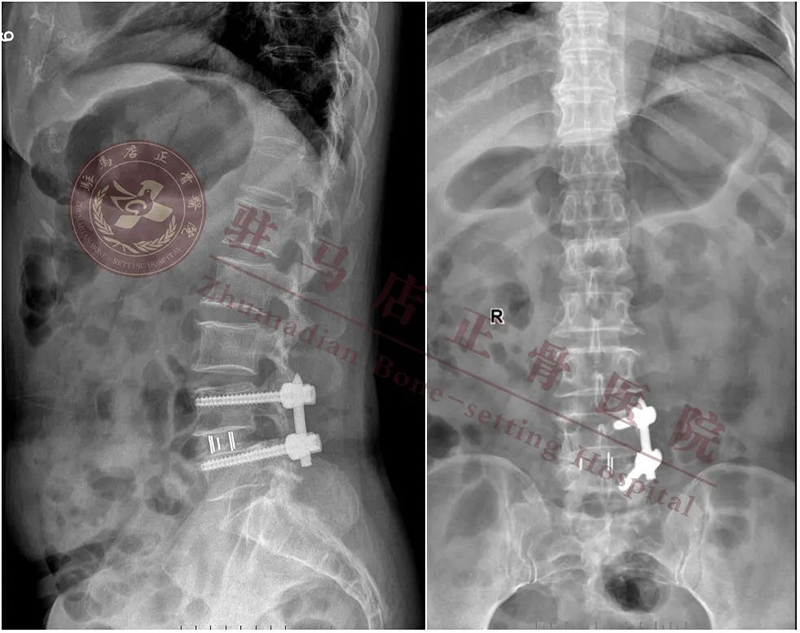

【诊 断】:1.腰椎管狭窄症(L4/L5); 2.腰椎间盘突出症(L4/L5); 3.腰4椎体滑脱(II度)

【术前计划】:通过影像等相关检查,明确诊断,根据诊断确定手术方式:经内镜下行腰4/5椎间盘切除、椎管扩大减压、椎间植骨融合复位、经皮椎弓根螺钉单侧内固定术

【拟行手术名称】:UBE镜下腰4/5减压融合固定术

术后影像